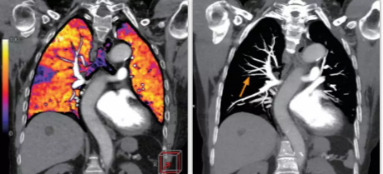

相比傳統成像方式,肺部柔性減影技術(shù)通過(guò)人工智能,對平掃數據和CT肺動(dòng)脈血管掃描數據進(jìn)行智能比對,解碼并識別各個(gè)器官(肺、氣管、肺動(dòng)脈、肺靜脈、主動(dòng)脈等)的空間位置,并在三維空間中進(jìn)行體素級的柔性配準,從而極大提升了不同序列數據的空間位置的一致性。通過(guò)肺部柔性減影技術(shù)可得到肺強化碘圖,可以顯示出傳統CTPA圖像看不到的小栓塞病變,提高了栓塞檢出率,其結果甚至可與SPECT吻合。

肺智能柔性減影成像功能發(fā)現亞段肺栓塞